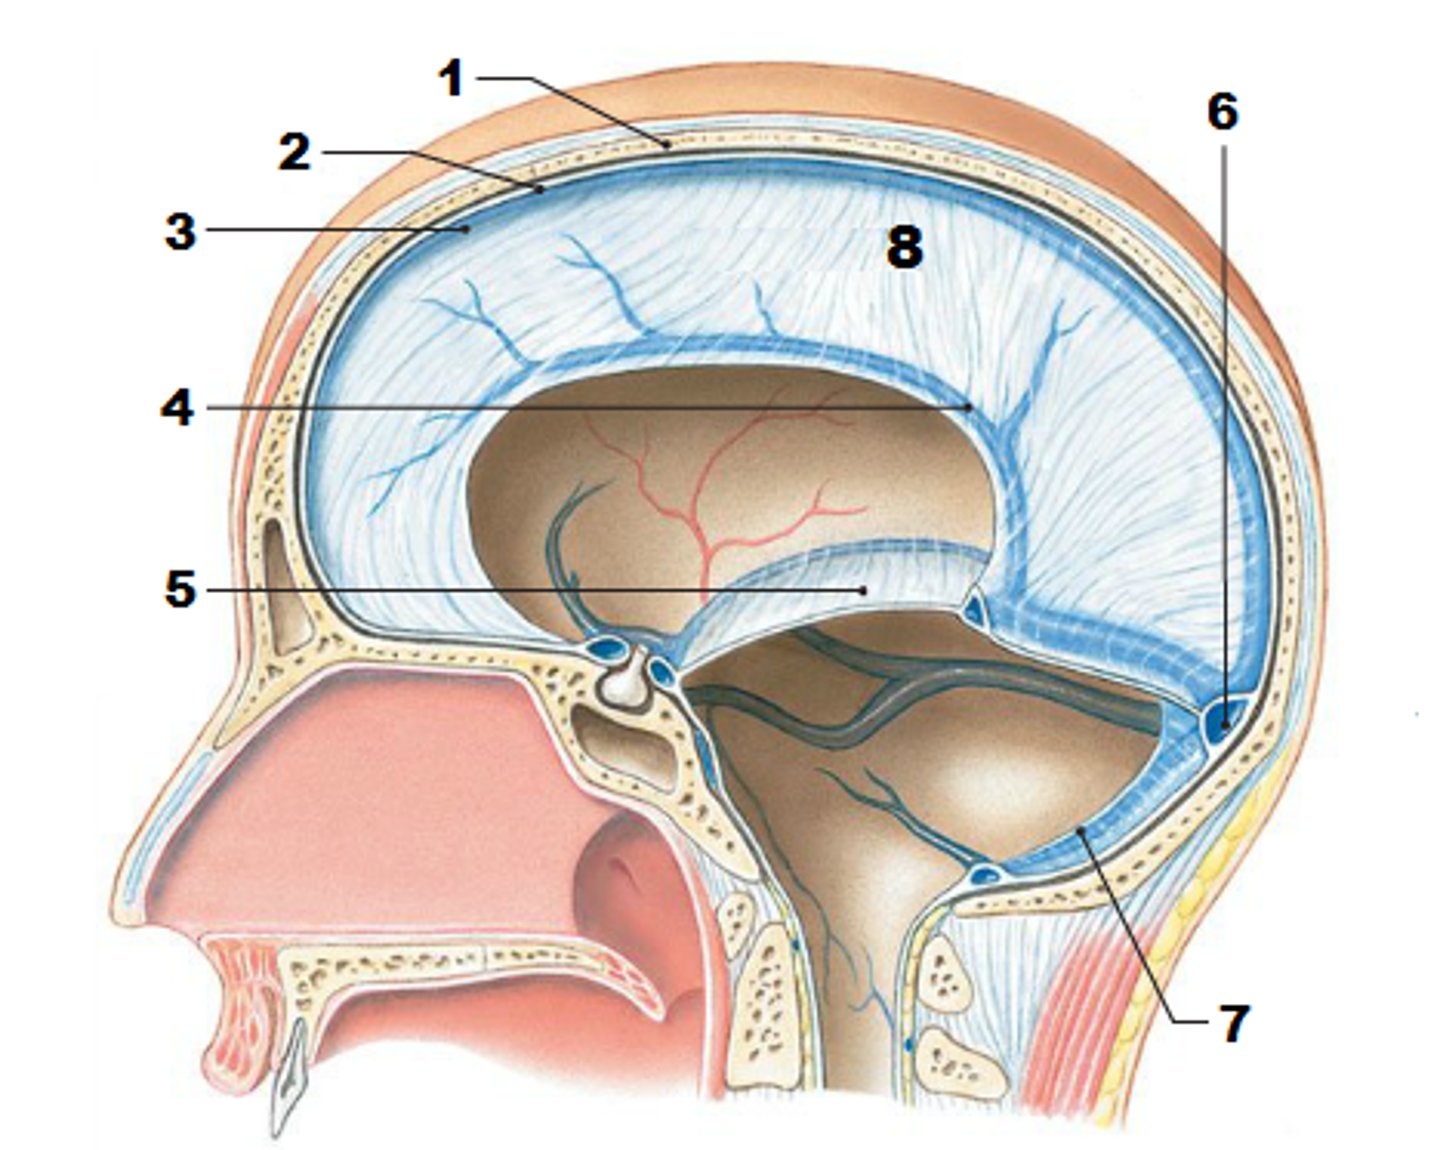

falx celebri

large, sickle-shaped, separates the cerebral hemispheres

tentorium cerebelli

2nd largest, crescent-shaped, separates cerebrum (occipital lobes) from cerebellum (arrow #5)

falx cerebelli

seperates the two hemispheres of the cerebellum. it lies inferior to the tentorium cerebelli, separating cerebellar hemispheres (arrow #7)

diaphragm sellae

smallest infolding covering pituitary gland & sella turcica

superior sagittal sinus

subdural space

space between dura mater and arachnoid mater

subarachnoid space